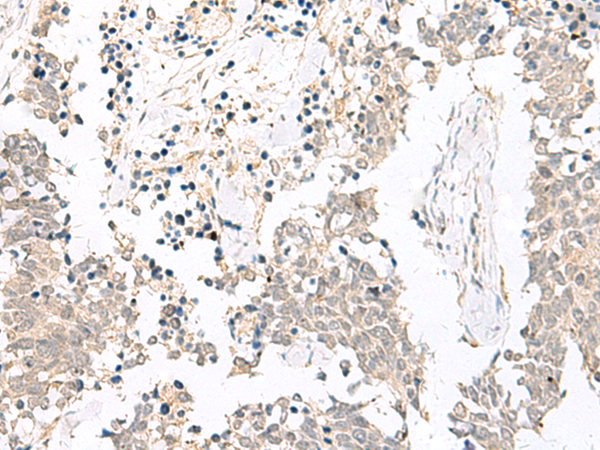

IHC positive control: |

Human lung cancer and Human esophagus cancer |

IHC Recommend dilution: |

20-100 |